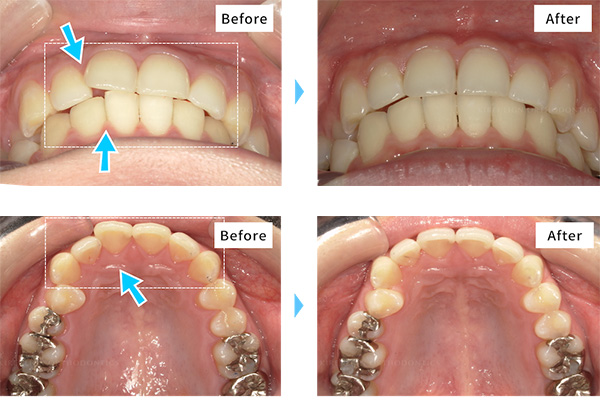

-

- 治療期間

- 約4ヶ月半(キレイラインを4回実施)

- 治療費用

- 160,000円(税込176,000円)

-

No

36130814

-

症状

すきっ歯,ガタガタな歯

-

再診料

(4回) 12,000円 (税込13,200円)

-

追加治療

なし

- ※効果には個人差があります。

- ※上顎左右2番矮小歯のため補綴予定です。費用は各提携クリニックによって異なります。

- ※補綴治療は、キレイライン矯正による矯正歯科治療の一環ではありません。患者様のご要望や症状により医師の判断のもと行われる「クリニックの治療」に該当しますので、詳細は提携クリニックに直接ご確認ください。